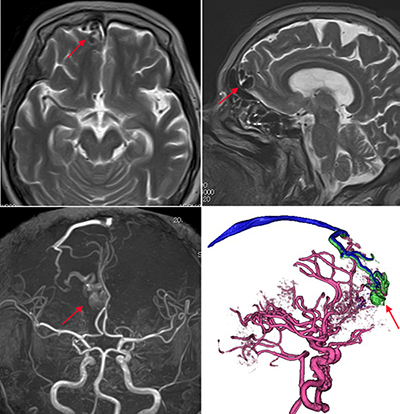

◆2025年2月発行の2刷りです。お値引きはしていません(交渉不可)。◆カバーに目立たない傷はありますが、使用せずに保管していたものなので、あまり使用感のない美本です。書き込み、断裁等の痛みもございません。◆WEB動画視聴用のロック解除キーは未使用です(問題なく動画見られます)。「dAVF・AVM(硬膜動静脈瘻・脳動静脈奇形)のすべて : 中枢神経系シャント疾患の治療戦略/22本のWEB動画付き」寺田 友昭 / 寺田 友昭 / 清末 一路 / 清末 一路定価: ¥ 17600#寺田友昭 #寺田_友昭 #寺田友昭 #寺田_友昭 #清末一路 #清末_一路 #清末一路 #清末_一路 #本 #自然/医療・薬学・健康